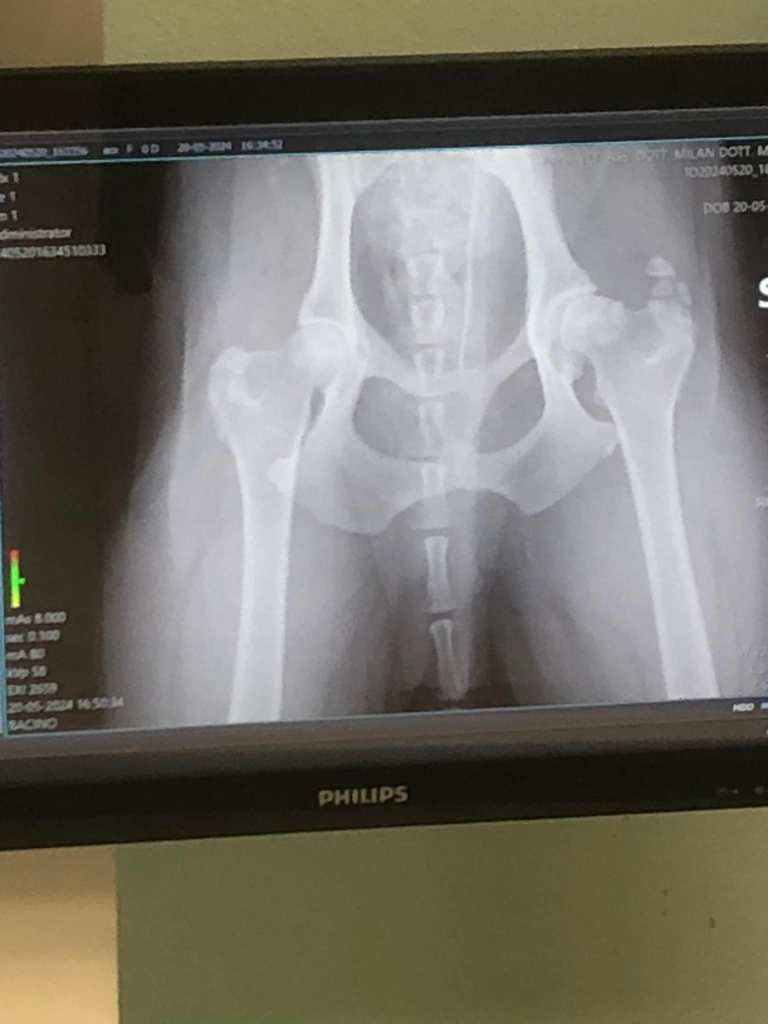

Then I left and slept in my car in a parking lot close to the vet’s office, so that Ace could do his follow up. For the anesthetic, x-ray, Librela shot, and pain medication, came to €112. This was a 10th of what I would have paid in England. The vet showed me the x-ray of Ace’s right hip having severe hip dysplasia. But the good news was that it wasn’t bone cancer. And for that, my spirits were lifted. In fact, the farther I got away from the Camp, the better I felt, like I needed to rip the band aid off, let go of the baby blanket. I needed to be brave again.